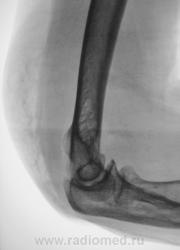

Травма неделю тому. Пациентка "особых" жалоб не предъявляла и была отпущена хирургом домой. Через неделю после травмы появилась отёчность мягких тканей по задней поверхности дистальной трети плеча и локтевого сустава. пациентка была направлена на рентгенографию локтевого сустава.

Произведена рентгенография. Ваше мнение уважаемые коллеги?

Продольный перелом головки луча с выраженным гемартрозом и параартикулярной гематомой...

Такие переломы довольно часты, и пропускаются тоже довольно часто